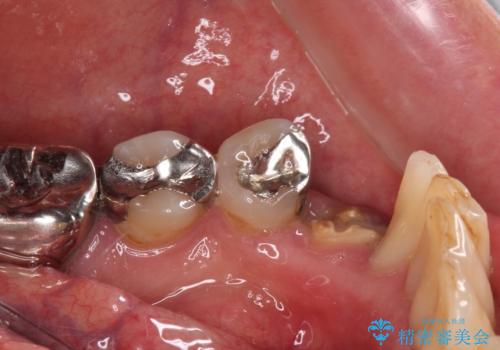

当該歯である犬歯は歯根が長く、安易に抜歯することはおすすめできないため、まずは部分矯正により歯根を引っ張り出し、その後歯周外科処置により歯槽骨や歯肉の状態を整え、最終的にはオールセラミッククラウンにて補綴治療を行うこととしました。

矯正治療中は汚れが溜まりやすく、歯肉からの出血が続きましたが、最終的には歯を保存して安定した状態で補綴治療を行うことができました。